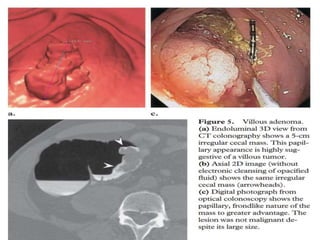

This document discusses colorectal polyps. It defines polyps and describes their types, including neoplastic and non-neoplastic polyps. It discusses adenomatous polyps in depth, noting their malignant potential increases with size over 1cm and villous architecture. Radiological diagnostic methods for polyps including single and double contrast barium enema and CT colonography are explained. The document provides an overview of polyp pathogenesis and genetic syndromes like FAP that increase cancer risk.